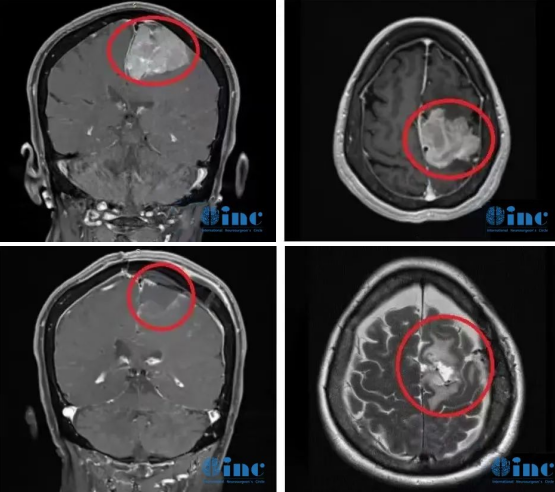

2019年,INC德国巴特朗菲教授曾4次来华,并在国内协作的三甲医院(苏州大学附属第一医院、苏州大学附属儿童医院、浙江大学医学院附属邵逸夫医院、无锡市第二人民医院等)开展疑难手术示范等,成功展示了多例在脑干、颅底、功能区等复杂病变(包括脑肿瘤/脑海绵状血管瘤/脑血管病变等)的全切及近全切手术之作。INC巴教授2019来华疑难手术示范掠影

2021巴教授来华疑难手术示范掠影2022作为江苏省卫生支撑计划中德国际合作交流项目,INC国际神经外科医生集团旗下组织世界神经外科顾问团(WANG)成员、世界神经外科联合会WFNS教育委员会主席、德国INI国际神经学研究所Helmut Bertalanffy(汉莫特·巴特朗菲)教授受邀再次来华学术交流及疑难手术示范。在INC合作的国内三甲医院——苏州大学附属儿童医院及苏州独墅湖医院,巴特朗菲教授与国内专家同台示范手术,在救治疑难病症患者的同时,切磋手术技巧、学术交流讲学,推进中外神经外科之间的良性互动。

除了进行疑难示范手术,INC德国巴教授还与上百名疑难患者的面对面沟通病情,就治疗问题答疑解惑。期间,巴教授还应邀参加线下及线上学术交流会议,进行疑难脑瘤手术示范教学直播,国内神经外科专家可与国际专家现场切磋、面对面探讨神经外科领域疑难问题及手术技巧。